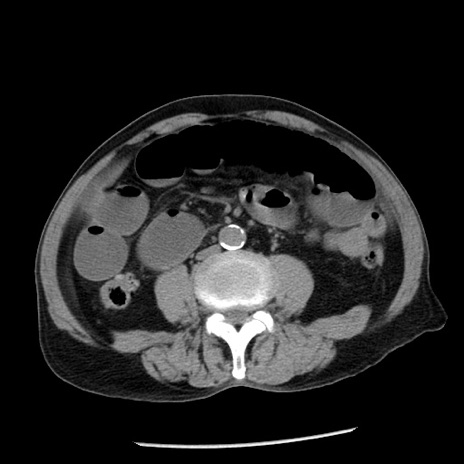

症例26(横断像)

【症例】80歳代男性

【主訴】嘔吐

【現病歴】昨晩2回嘔吐あり、今朝になっても嘔吐あり。来院。

【既往歴】胃潰瘍

【身体所見】意識清明、BT 37.6℃、BP 166/95mmHg、HR 100bpm、SpO2 97%、腹部:平坦・軟、腸蠕動音聴取良好、圧痛なし。

【データ】WBC 21900、CRP 1.46